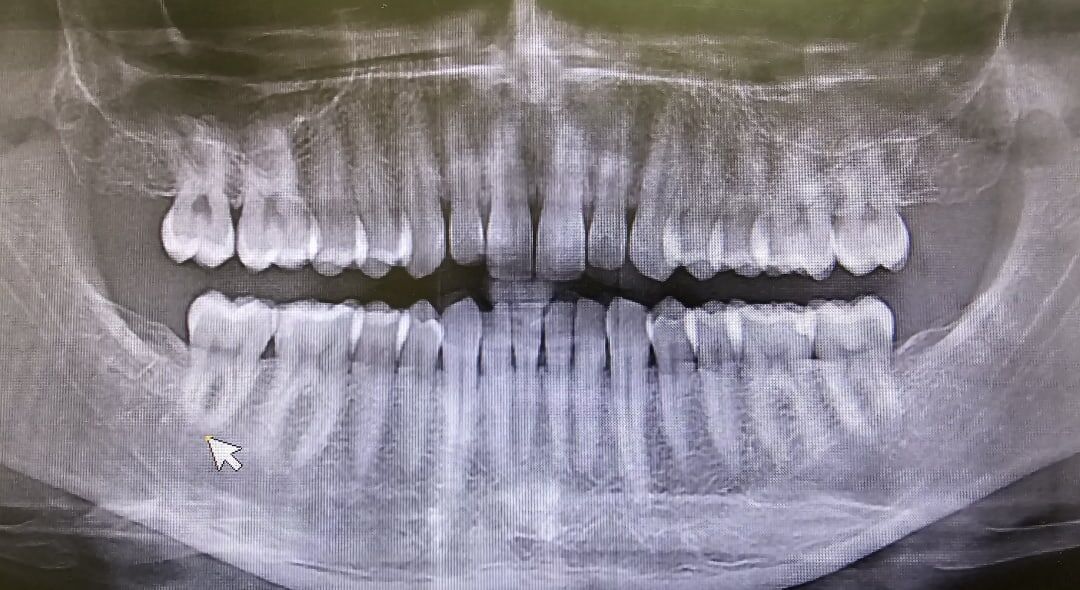

2. Рентген диагностика и фотопротокол. Снимки назначит врач, те которые необходимы для того или иного лечения. Как правило это панорамный (ОПТГ) или объёмный (КЛКТ) снимок. В современной стоматологии не мало внимания стоит уделить и "дентальным" фотографиям (снятые на профессиональный фотоаппарат) макро фотографии зубов и зубных рядов.

ОПТГ (панорамный снимок)